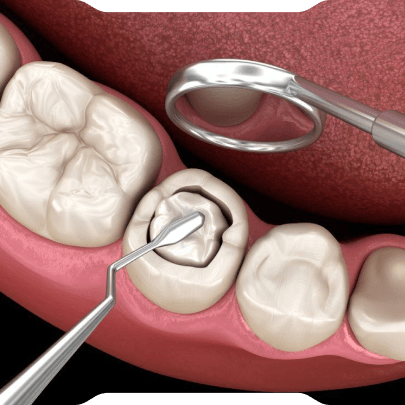

Kompozit dolgu; seramik ve silika parçacıkları içeren, ışıkla sertleşen modern bir restoratif maddedir. Dişe kimyasal olarak bağlandığı için sadece çürüklerin tedavisinde değil, dişlerin şeklini değiştirmek veya kırıkları onarmak (bonding) amacıyla da güvenle kullanılır.

- Hazırlık: Çürük doku temizlenir ve diş dolguya hazır hale getirilir.

- Uygulama: Dolgu malzemesi tabaka tabaka yerleştirilir ve her aşamada özel bir ışık cihazıyla sertleştirilir.

- Form Verme ve Polisaj: Dişin çiğneme fonksiyonuna uygun anatomik form verilir ve yüzeyi cilalanarak doğal diş parlaklığına ulaştırılır.